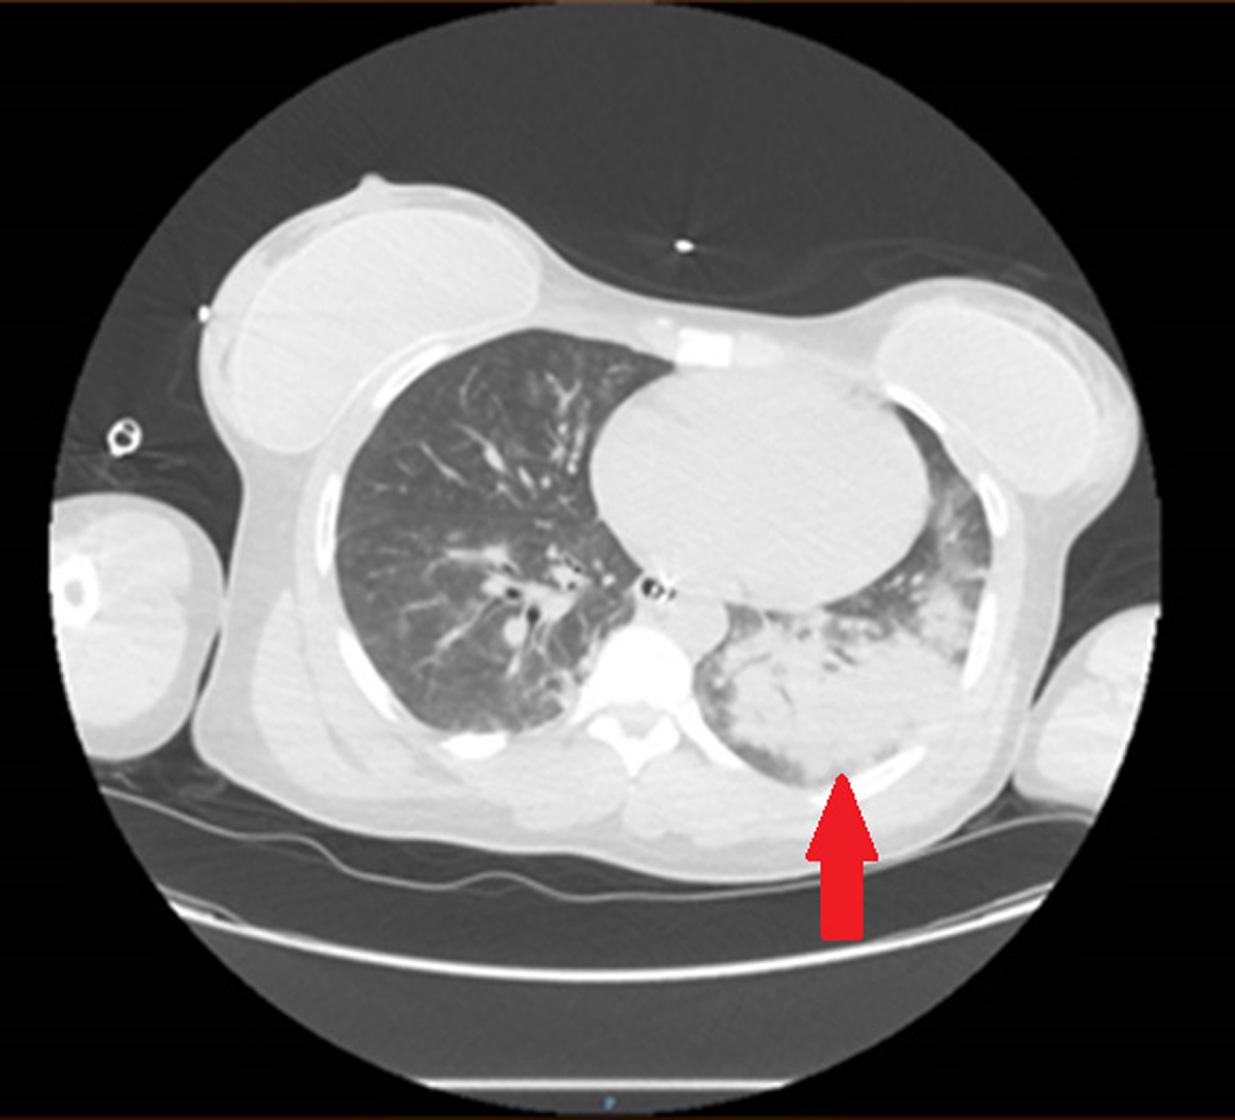

Achestradiograph(CXR)(Image1)showedalargehiatal herniawithtracebilateralpleuraleffusionsanddisplacement ofthegastricbubbletotheright.Computedtomography (CT)withcontrastofthechest/abdomen/pelvis(Images2 and 3)demonstratedalargehiatalherniawithmostofthe stomachinthechest,associatedvolvulus,bilateralpleural effusions,rightgreaterthanleft,andacomplex,partially fluid-filledcollectionalongtheposterioraspectofthehiatal

Anterior-posteriorchestradiographdemonstratinglarge hiatalherniawithdisplacementofthegastricbubble(arrow)from lefttoright.

Image3. Transverseviewofcomputedtomographyofthechest/ abdomen/pelviswithanarrowindicatingpartially fluid-filled collectionposteriortoalargehiatalherniasuspiciousfor esophagealperforation.

Image1. Image2. Coronalviewofcomputedtomographyofthechest/ abdomen/pelvisshowinglargehiatalhernia(arrow).Thepatientunderwentanexploratorylaparotomy,which confirmedthepresenceofanesophagealrupturenearthe squamocolumnarjunctionandrevealedthepresenceofa gianthiatalherniawithanassociatedupside-downstomach. Surgicalrepairoftheesophagealperforationandgastropexy wasperformed.Thepatientwasadmittedtothesurgical intensivecareunitforatotalof fivedaysduringwhich shehadanepisodeofatrial fibrillationwithrapidventricular responsethatresolvedaftermetoprololanddiltiazem.